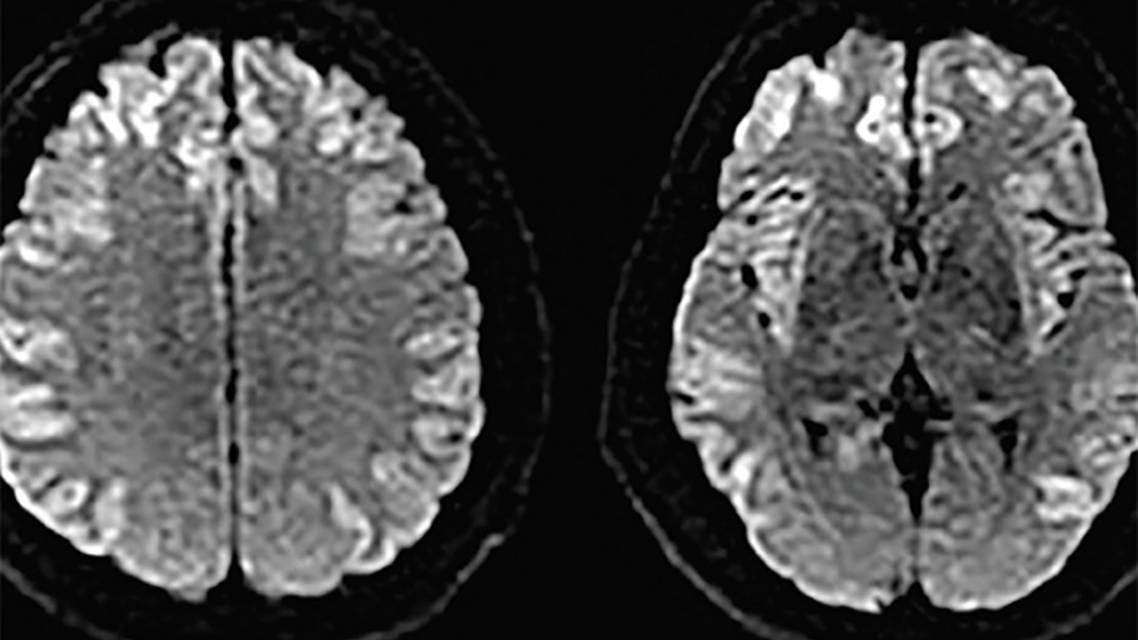

Noncontrast head CT and CTA of the head and neck were unremarkable on the day of admission. Head CT was repeated after seizure activity developed and showed sulcal effacement and loss of grey white differentiation, concerning for cerebral edema. A brain MRI showed diffusion restriction in the insular, cingulate, frontal, temporal, and parietal cortices (Figure 1). Mr. L’s EEG was notable for diffuse slowing while being treated with propofol; no epileptiform discharges were seen.

Imaging is characterized by extensive cortical involvement including a predilection for the insular and cingulate cortex.10,11 Cortical changes are potentially reversible, but can result in varying degrees of atrophy of the insular and cingulate cortex.5 The degree and duration of hyperammonemia may be reflected in the severity of imaging findings.